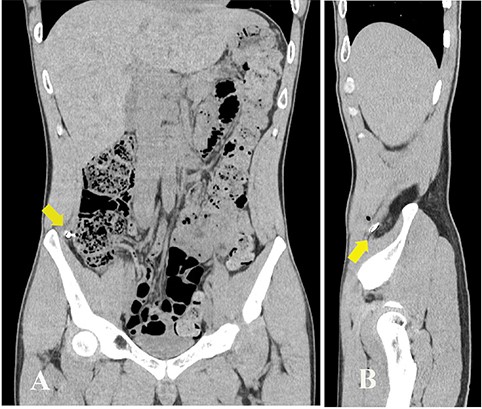

A 27-year-old man working in a forging factory presented to our hospital with acute abdominal pain. He reported that, 3 hours before presentation, a metal fragment came flying from the operating power hammer, which molded molten metal into the desired shape by striking it. Although he was wearing protective clothing, the fragment penetrated through it and caused sharp pain. Physical examination revealed a 1 cm wound, resembling a stab wound above the right iliac crest (Fig. 1A). The patient experienced localized abdominal pain around the wound; however, there were no signs of peritoneal irritation. His vital signs were stable and laboratory data showed no abnormalities except for a slightly increased C-reactive protein level of 0.91 mg/dL (reference range, 0–0.14). A spine abdominal radiograph showed a 1 cm-sized radiopaque object in the lower right abdomen (Fig. 1B). An abdominal computed tomography revealed a radiopaque object near the peritoneum; however, its exact location being extraperitoneal or intraperitoneal could not be determined (Fig. 2A and B). The abdominal cavity did not have free air or fluid retention. The patient was diagnosed to have a foreign body near the peritoneum and surgical removal was planned. The operation was performed using single-incision plus one-port laparoscopic surgery (SILS plus one). A 1.5 cm longitudinal incision was made at the umbilicus to access the abdominal cavity, after which the wound retractor (Smart Retractor XS; TOP Corp., Tokyo, Japan) was inserted. It was mounted to a single-port access device (Free Access; TOP Corp., Tokyo, Japan). Subsequently a 5-mm trocar was placed just above the pubic symphysis. Laparoscopic inspection following pneumoperitoneum revealed no damage to the peritoneum or internal organs (Fig. 3A). Although we assumed the foreign body was located in the abdominal wall, laparoscopic inspection could not confirm its position. Real-time fluoroscopy was used to locate the fragment. The nearest peritoneum was incised and the abdominal muscle was dissected until the foreign body was observed (Fig. 3B). It was found embedded in the transversus abdominis muscle (Fig. 3C) and was safely removed using forceps (Fig. 3D). The object was 1.5 cm long and sharp at both ends (Fig. 4). The patient was discharged from our hospital after a good postoperative course.

(A) Photograph showing a 1 cm entrance wound, similar in appearance to a stab wound above the right iliac crest (arrow). (B) Spinal abdominal radiograph showing a 1 cm-sized radiopaque object in the lower right abdomen (arrow head).